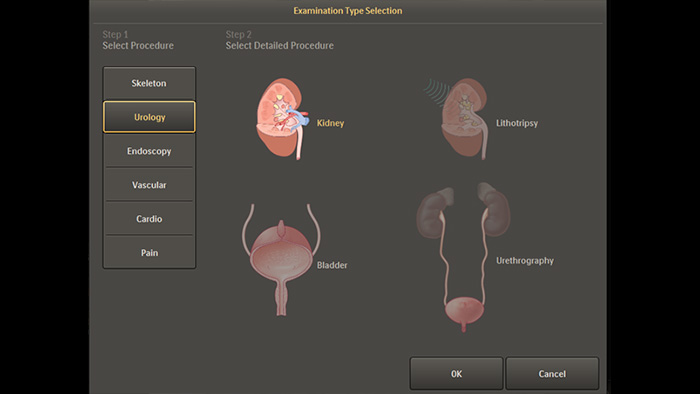

Configuración anatómica predeterminada para los procedimientos de urología y endoscopia

Los parámetros de imágenes predefinidos para diferentes procedimientos y características anatómicas, que se pueden personalizar por aplicación, aumentan la confianza clínica y la eficiencia para los diversos procedimientos y pacientes de cada día.